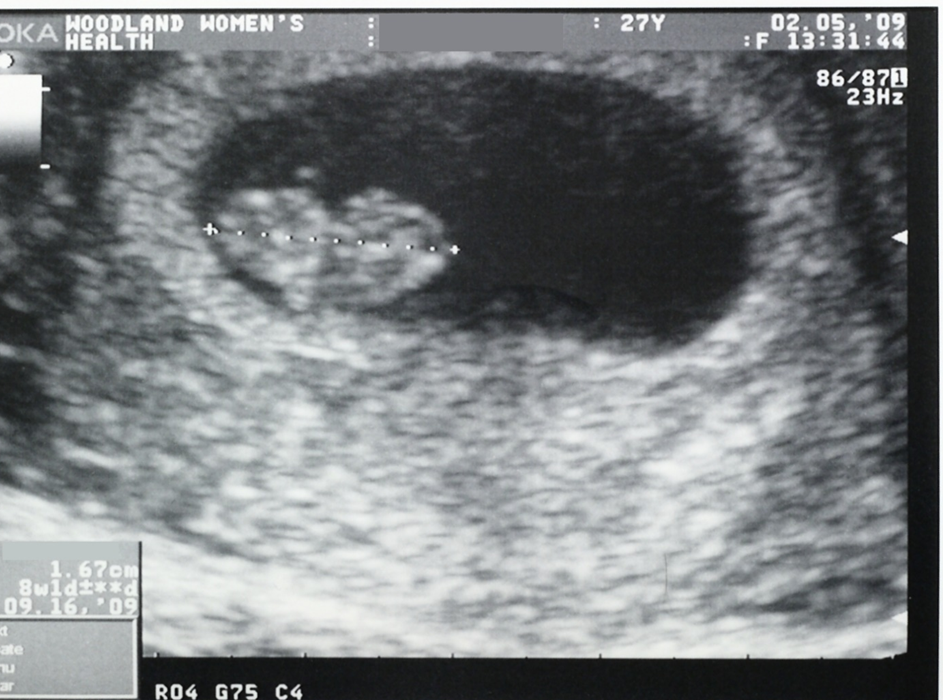

What is the most accurate way to date pregnancy?

crown rump length

What measurement remains accurate until the 8th week?

MSD – Mean Sac Diameter

CRL is typically done up to ____weeks

12 (can be done up to 14 weeks)

Cardiac activity should definitively be seen in a CRL measuring

5-7 mm